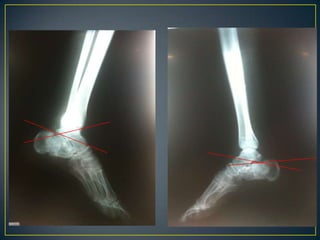

IIIIVVRADIOGRAFÍASSIMPLES 		    TOMOGRAFÍApreoperatoria

II  BTC  preoperatoriaIncongruencia subtalica  post.   :  90 %Conflicto maleolar externo            :  80 %Lesión calcáneo-cuboidea             :  40 %

Crosby y fitzgibbon y de Sanders Tipo I son fracturas no desplazadas. Tipo II son dos partes o dividir las fracturasTipo III son de tres partes o las fracturas de la depresión de división. Tipo IV fueron de cuatro partes o muy conminutas fracturas articulares. Basada en TAC: lesiones complejas